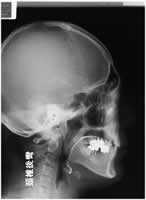

さて、顎の大きさや形はどのように診断するのでしょう。それは、横顔のレントゲンで顔面軸という名称の角度を測定して診断しているのです。この角度は、 日本人の平均が86度です。それよりも小さいと顎が後ろに下がっていびきをかきやすい体質になります。そして、80度より小さい場合は遺伝する可能性があ ります。一方、米国人の顔面軸は90度と日本人よりも大きく、そのおかげで米国人は多少太ってもいびきをかきません。日本人の中でも、縄文時代の日本人は 顔面軸が大きかったと想像されております。その後に弥生人が渡来してきて、顔面軸が小さい現代の日本人が形成されました。面白いことに、現代日本人でも縄 文系に近い人と弥生系に近い人がいて、同程度の無呼吸症なら縄文系の患者は肥満が強く、弥生系の患者では肥満が軽いことが知られております。皆さんの顔面 軸を計測してどちらの系統に近いか診断できれば、その骨格での限界の体重、すなわちいびき症が発病する体重を予測できるのです。

[顔面軸の図]

この手術の歴史は古く、写真はその一例で、手術後の写真に金属のプレートやネジが残っているのが判ると思います。 なんでまた、世界の睡眠医学をリード するスタンフォード大学がこの手術に注目しているのか、それはこの手術が唯一の根本的治療法だからです。 それともう一つ、睡眠時無呼吸症候群を発症させ ずに未然に防ぐためのヒントが隠されているからなのです。

[MMAの説明]